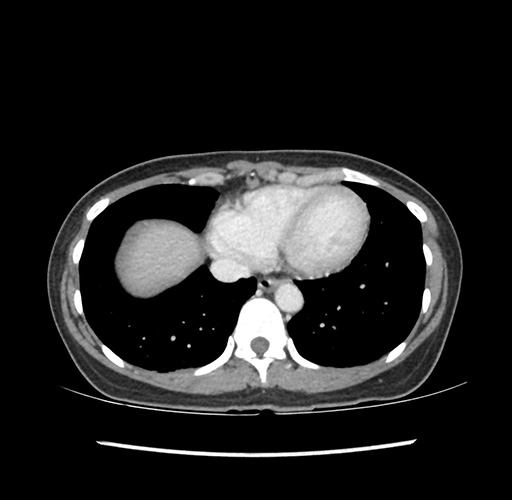

Imaging Analysis

Look through the patient's CT scan to identify any areas of concern for the necessary procedure.

Based on your CT findings, which issue(s) would give reason for "planned slowing down moment(s)" in this case?